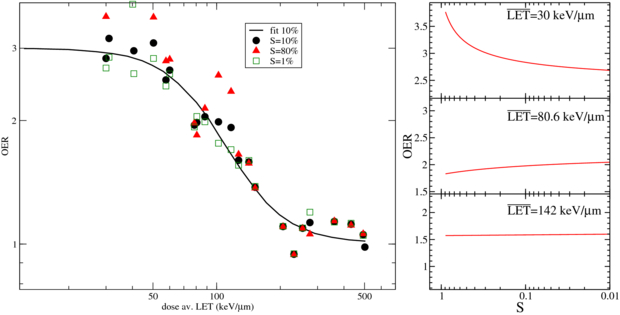

A confirmation of the very small OER dependence on the dose and then of the validity of an approximation employing a dose modifying factor, arises from the analysis of these data and specifically comparing the fit obtained on the 10% survival data with the other data reported in that collection (Furusawa et al 2000): in figure 1 the survival dependence is extracted through inserting the reported LQ parameters in (5), and it is especially visible how, at increasing LET, the assumption of the dose modifying factor becomes even more safe, as also reported in Wenzl and Wilkens (2011b).

Figure 1. Dose averaged LET dependence of OER at pO2 = 0, obtainable from experiments on V79 cells (Furusawa et al 2000): left panel, OER resulting data at different survival levels and compared to the fit provided in this work and performed using only the 10% values; right panel, survival dependence of observed OER at different  levels.

levels.

The complete surface is shown in figure 2, with the parameter values introduced above. Independent measurements performed at GSI, with the techniques described in following section 4, confirmed the behavior of the fully anoxic curve, and additionally gave some insights of the partial hypoxic conditions with a set of measurements at pO2 = 0.5%, for a single LET value, which resulted, after averaging on the three performed experiments, in very good agreement with the corresponding computed curve. These measurements were performed on CHO-K1 cells, a tissue type similar but not identical to the Japanese one, thus confirming the above mentioned very low tissue dependence. The complete original experimental data, partially reported in Tinganelli et al (2011) and Durante et al (2012), will be published separately (Tinganelli et al 2013), while the extracted OER values are summarized in figure 2 and superimposed to our independent parameterization. There, the numbers close to the points correspond to the number of experiments performed; and when only a single experiment was possible, mean and standard deviation are derived from the colonies counts. These data also confirmed the almost negligible dependence on ion type, for a discrete range of Z, once the dose average LET is considered, as also found in Furusawa et al (2000).

Figure 2. OER dependence on LET and oxygen concentration, in the parametric description provided in this work and, in the lower panel, selected surface cuts compared to independent experimental data (Tinganelli et al 2011, Durante et al 2012). The number of performed experiments is also shown close to the corresponding average point, see text for details.

Download figure:

Standard image High-resolution imageThe complete lack of experimental data (except the single one reported) at intermediate values of pO2 and LET, impose a serious uncertainty to the present as well as to any other model, especially since these are the most relevant conditions for treatment planning. In fact, the typical  values in an ETI with carbon ion are between 70 and 130 keV μm−1, exactly in the region where the slope of the OER surface is maximum and the most typical values for hypoxic tumors are for a pO2 between 0.15 and 2%. We want to point out that the single measurement we reported at 100 keV and pO2 = 0.5% is the first one in this region, which should be definitely explored more extensively.

values in an ETI with carbon ion are between 70 and 130 keV μm−1, exactly in the region where the slope of the OER surface is maximum and the most typical values for hypoxic tumors are for a pO2 between 0.15 and 2%. We want to point out that the single measurement we reported at 100 keV and pO2 = 0.5% is the first one in this region, which should be definitely explored more extensively.